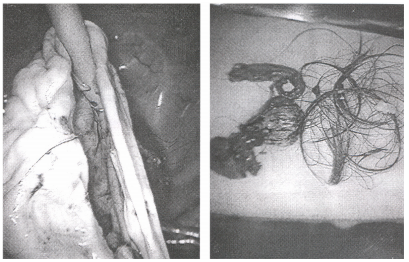

36 一位 20 歲女大學生因急性腹痛而接受手術,取出卵巢腫瘤(如下圖所示),則下列診斷何者最正確?

(A) 卵巢外孕 (B)卵巢畸胎瘤 (C)卵巢單純囊腫 (D)卵巢黃體囊腫